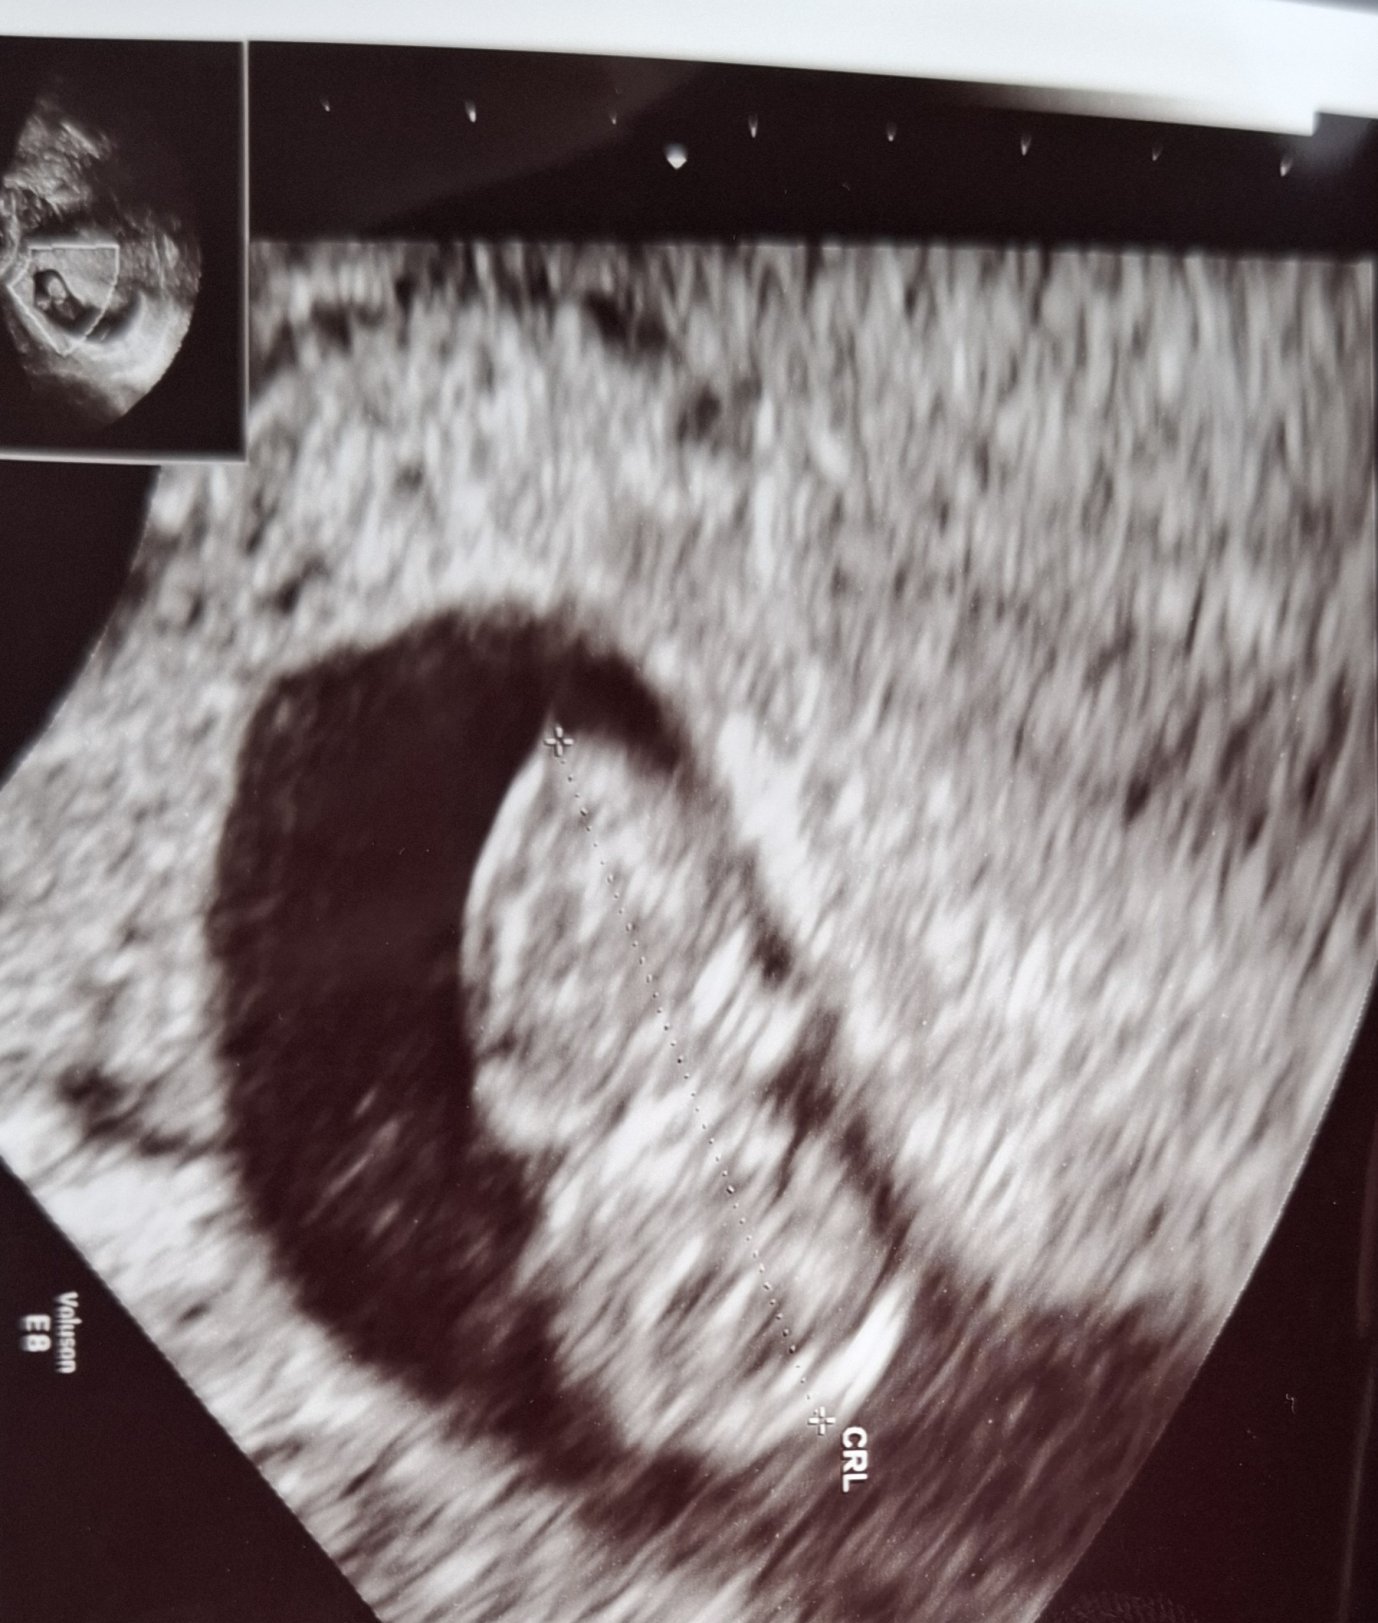

Плодът отговаря на 9с и 4дни. Термина ми идва за 16.07. Попринцип съм с много дълъг цикъл, и късна овулация, и е очаквано да закъснее според лекарските изчисления. Но Реално плодът до 10 седмица си има всичко вече. И след това само си расте. С предната бременност ходих на морфология в 11 и толкова хубаво беше оформено бебето че аз не вярвах, но лекаря тогава така ми обясни, че до 10 седмица всичко е образувано. Но да днес се видяха и ръчъчките и беше интересно , на фона на всичко останало с малко въображение на снимката си прилича на бебе вече.